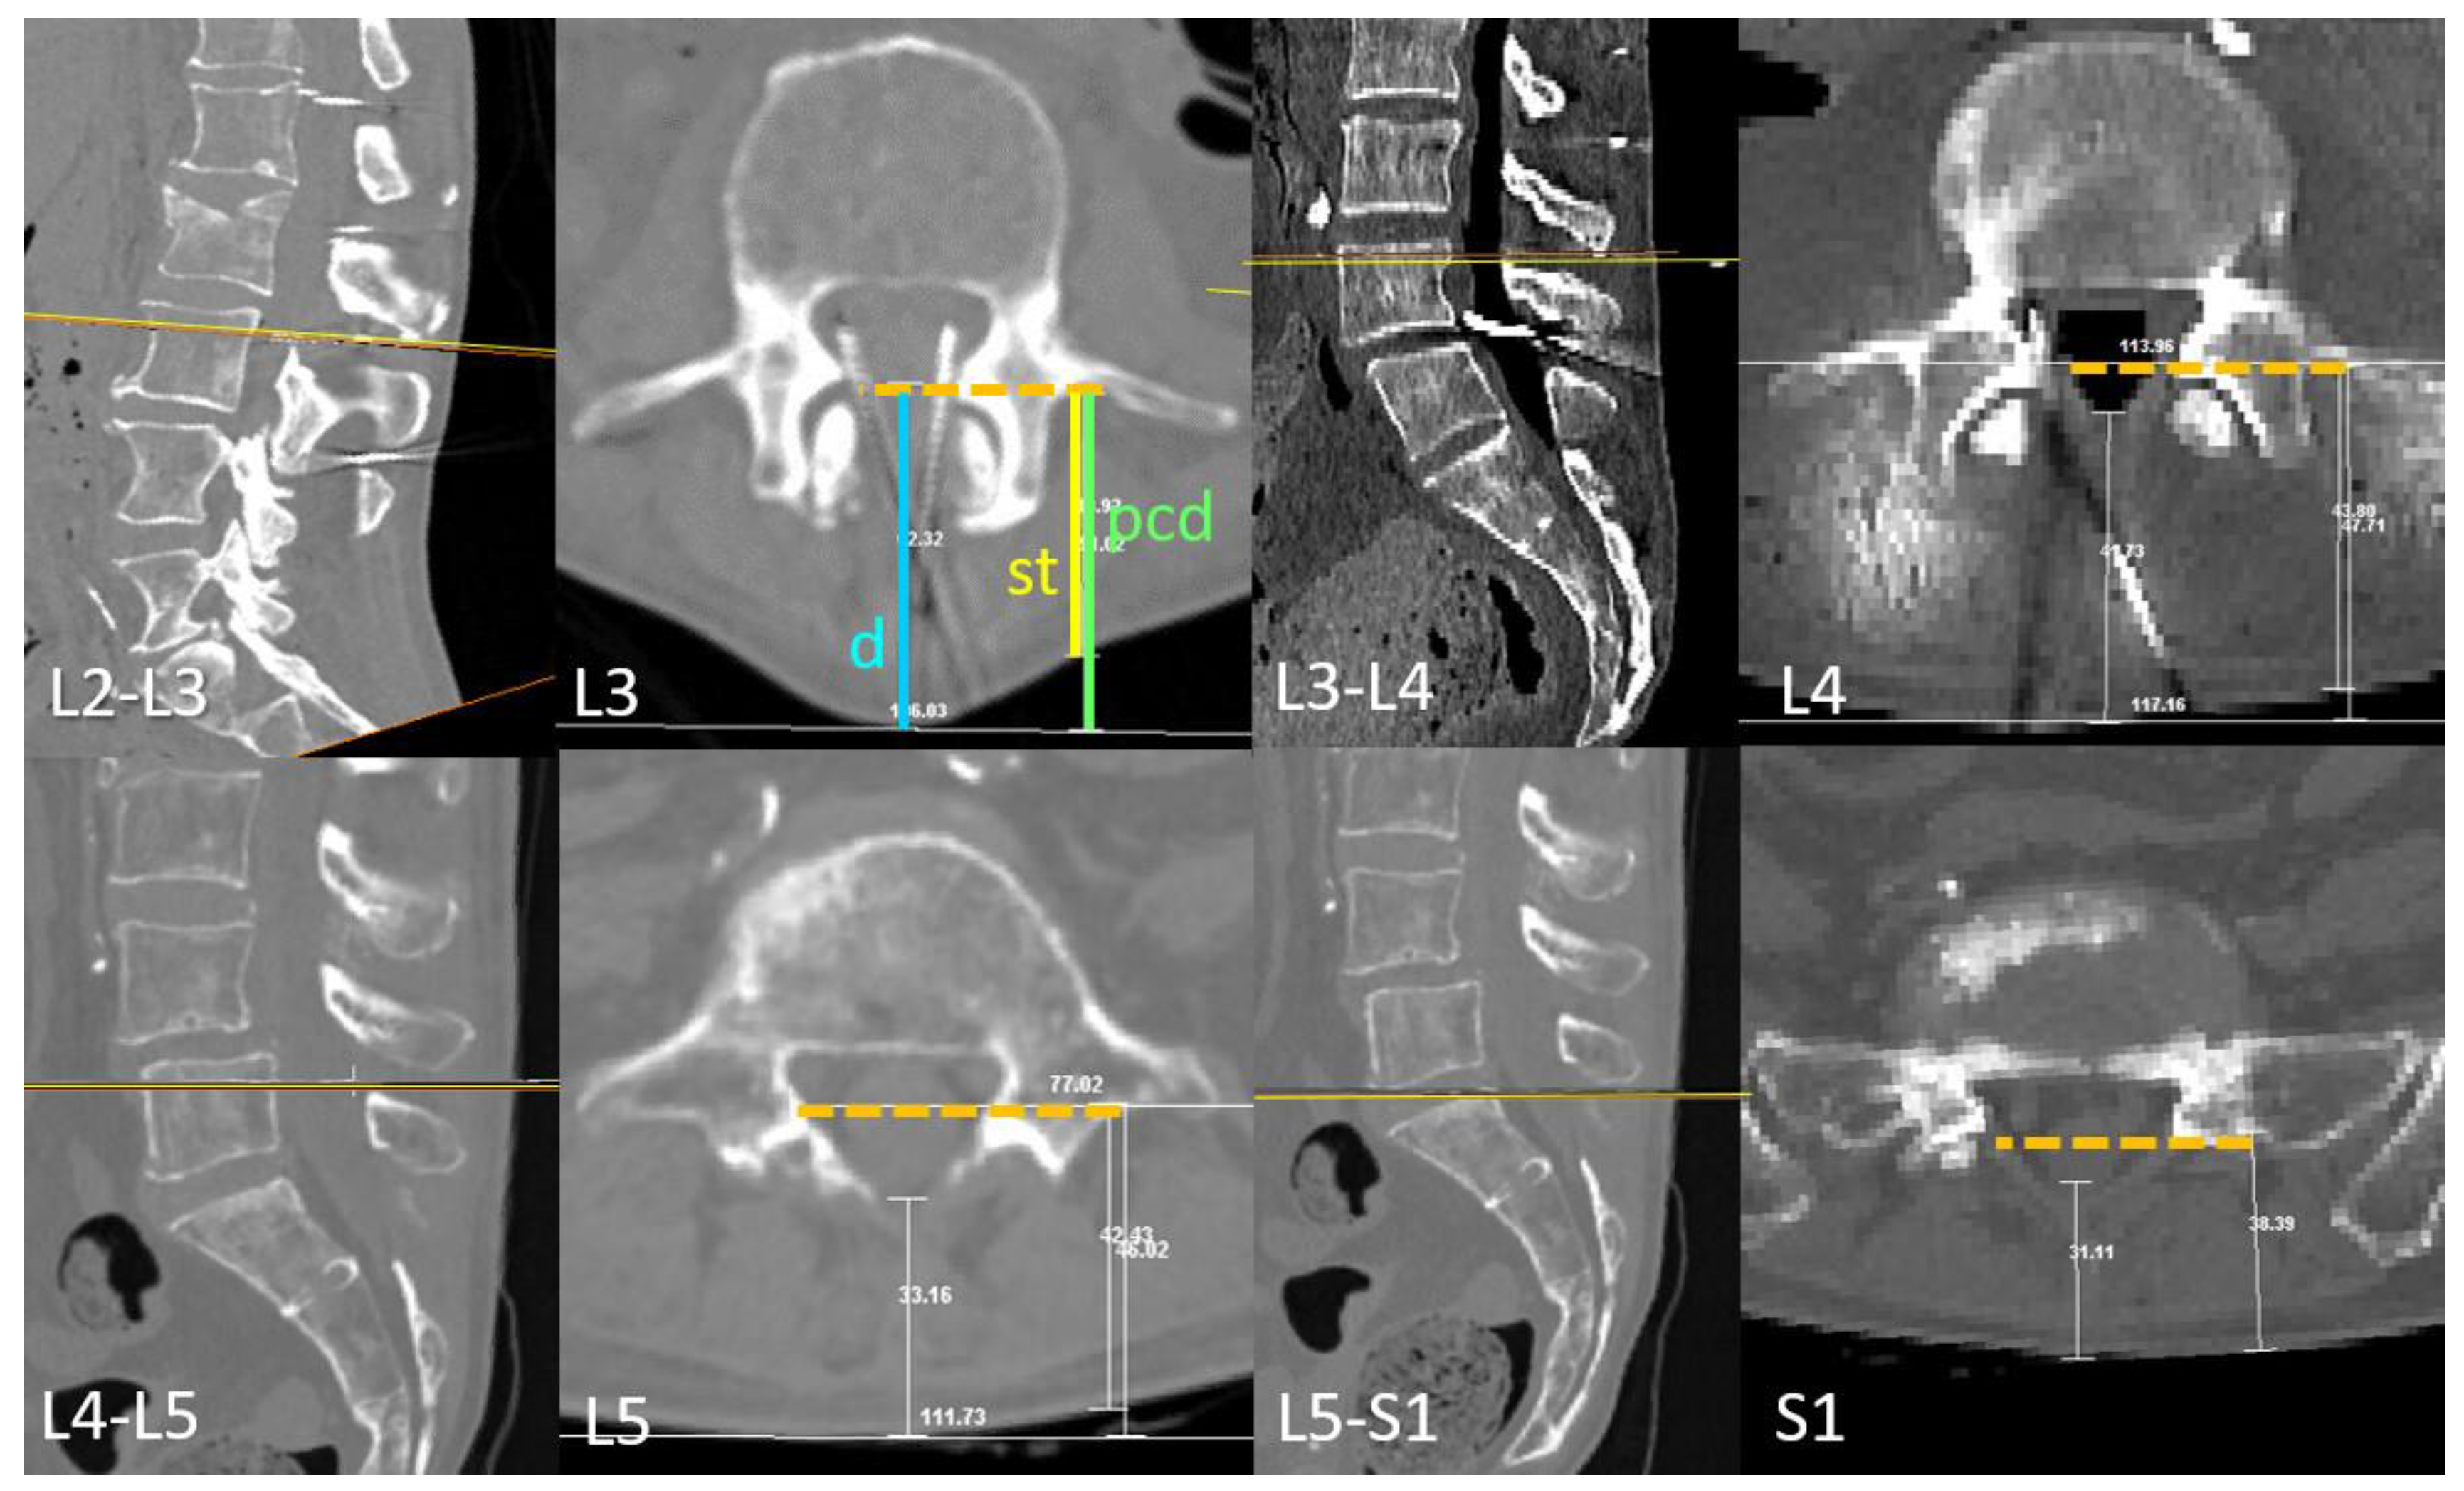

2.1.1. Transverse Process and Dural Sac Alignment.

2.1.2. Medial and Paramedian Paths for Perpendicular Needle Insertions.

3.1. Transverse Process and Depth Level Within the Dural Sac